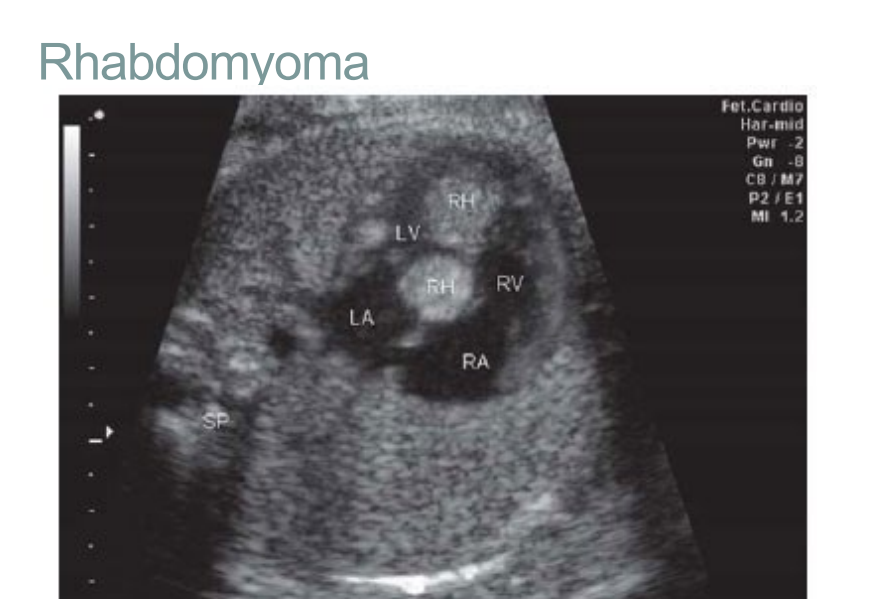

what is the most common Fetal Cardiac Tumors?

Rhabdomyoma

Rhabdomyoma, has a high association with what? Can you descibe how this tumor can be and where would it be found?

High association with tuberous sclerosis

May be a single tumor or multiple tumors in ventricles or IVS

can you decribe the obstruction it has?

what are the abnormalities it has?

what can this cause to the fetal?

Atrioventricular valve regurgitation and intracavitary obstruction

Arrhythmias and conduction abnormalities

May cause fetal myocardial dysfunction and hydrops